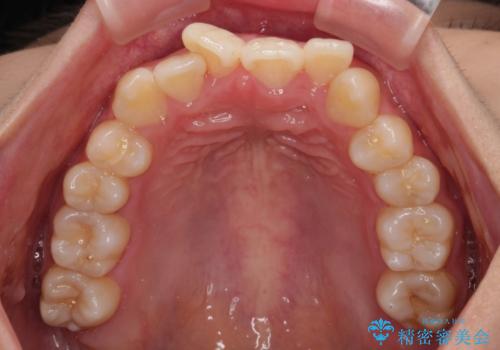

- 前歯のデコボコと唇の閉じにくさを気にして来院された患者様です。

単純に上下左右の第一小臼歯4本を抜歯して口元の突出感を改善することも考えられましたが、上顎骨よりも下顎骨の幅が広いため、より良い咬み合わせを達成することを目的として、急速拡大装置を用いて上顎骨を拡大することとしました。